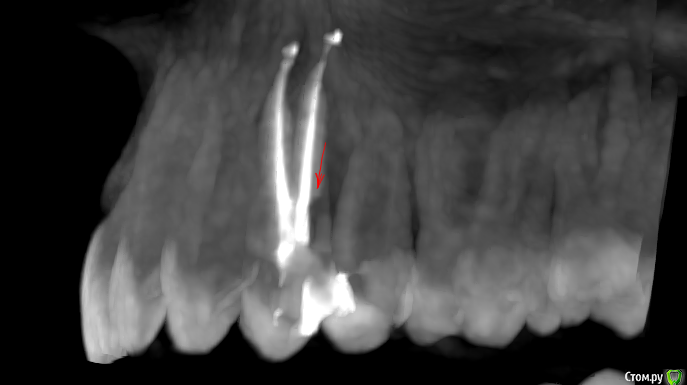

Прикрепляю скриншоты КТ. Подскажите, пожалуйста, что это может быть под красной стрелкой на снимках 2 и 3?

post-58215-0-06349000-1573918592_thumb.png